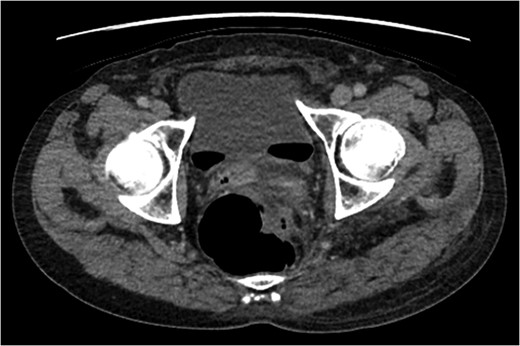

A rare complication of diverticular disease is the formation of fistulas, most commonly either colo-vesical or colo-vaginal. We present the unusual case of a perforated sigmoid diverticulum forming a colo-gluteal fistula and presenting initially as a gluteal abscess in an otherwise asymptomatic patient. After drainage of the gluteal abscess, the patient re-presented with faecal loss from the abscess drainage site. Imaging revealed fistulous communication between the sigmoid and the left obturator internus muscle, tracking to the gluteus maximus with associated abscess and cutaneous communication to the site of previous drainage. The patient underwent an emergency Hartmann's procedure with lay open/abscess drainage of the gluteal cavity. Post-operatively the patient experienced continuing discharge from the gluteal fistula despite repeated drainage and debridement causing considerable morbidity, inconvenience and misery. Clinicians should maintain a high index of suspicion when presented with a gluteal abscess and should consider the possibility of an intra-abdominal source.

An emergency Hartmann's procedure was performed under general anaesthetic through a lower midline incision as well as lay open of the perineal fistula. On opening the abdomen, a perforated diverticulum was identified extending into the left lateral pelvic wall. A standard Hartmann's procedure was performed, with sigmoid colectomy, division of rectum at recto-sigmoid junction and a tension-free stoma formed in left hypochondrium. The left buttock abscess cavity extended by a further 2–3 in. and the cavity then packed.